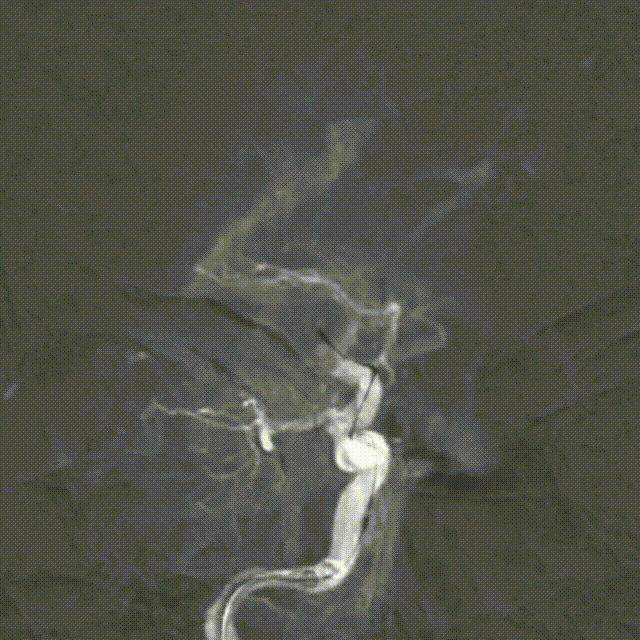

右侧大脑中动脉起始部闭塞,左侧前交通开放,左侧大脑前动脉通过软膜支代偿,大脑后动脉通过软膜支代偿,侧支代偿可,考虑粥样硬化合并急性闭塞的可能。

释放Syphonet®取栓支架 5*35mm,造影显示:支架释放效应可疑阳性。

造影:考虑局部血栓可能。

“SWIM”技术取栓,行血栓廓清。

取栓后造影,M1再通,局部狭窄可能,前向血流延迟。

M1局部狭窄,合并小血栓可能。